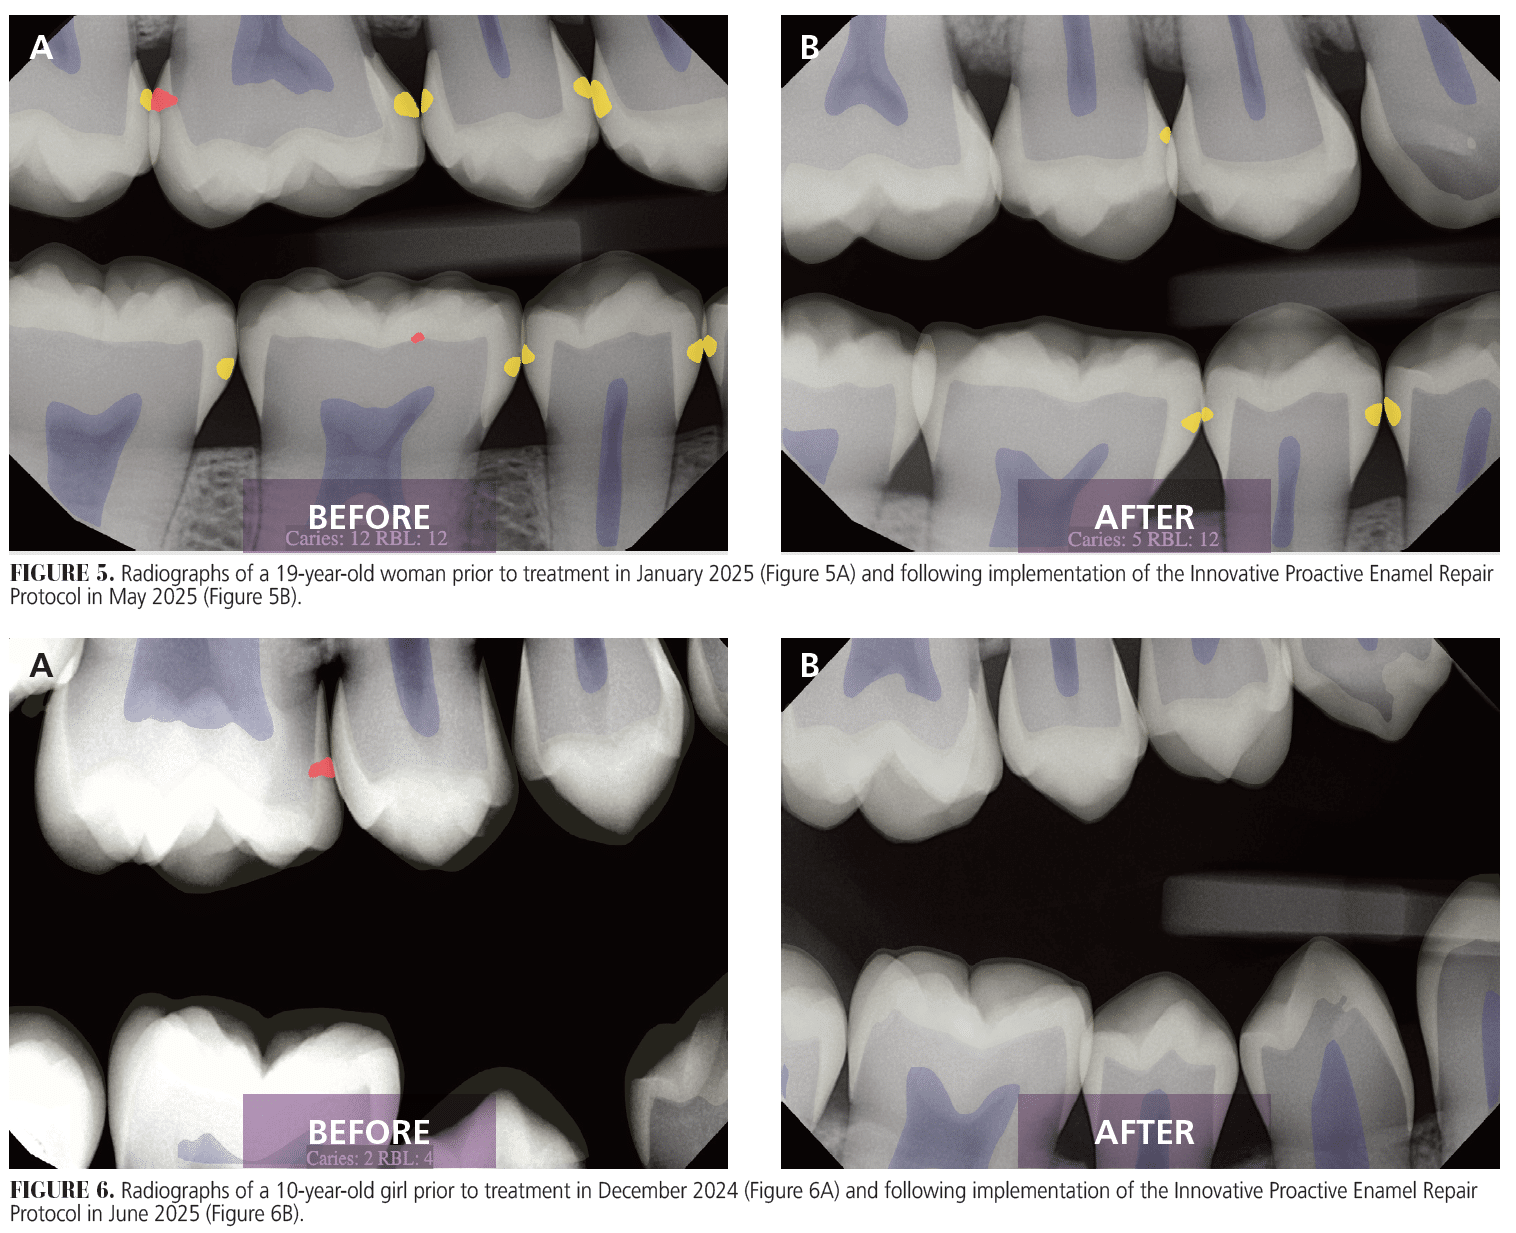

In 2024, I documented outcomes directly attributable to IPERP (Figures 4 and 5). Treatment acceptance reached 95%, driven by the clarity of diagnostic visuals and the simplicity of the noninvasive intervention. IPERP has easily integrated into our existing workflows and allowed us to be more efficient, without auxiliary staff involvement or additional chair time.